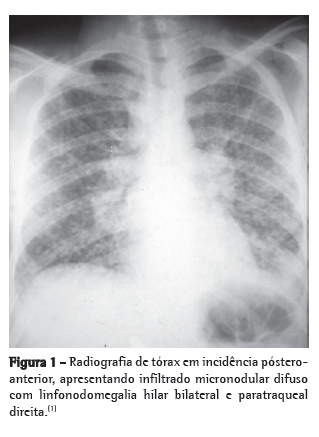

Exames radiográficosOs exames radiográficos não são específicos para o diagnóstico dessa micose. Na histoplasmose pulmonar aguda, o aspecto radiográfico mais frequente é a presença de linfonodomegalias hilares bilaterais e mediastinais associadas a infiltrado reticulonodular peri-hilar bilateral (Figura 1). Porém, linfonodomegalia hilar unilateral, infiltrado intersticial reticulonodular difuso, cavidades e nódulos difusos ou isolados podem ser encontrados. Na histoplasmose pulmonar crônica, o aspecto radiográfico se assemelha ao da tuberculose do adulto ou de reinfecção, isto é, infiltrado progressivo em lobo superior, cavidades e sinais de fibrose. O alargamento do mediastino pode ser visto principalmente na TC de tórax nos casos de histoplasmose granulomatosa e fibrose mediastinal. Nódulo solitário ou nódulos múltiplos com calcificação central são muito característicos da forma nodular, isto é, do histoplasmoma.(1-5)